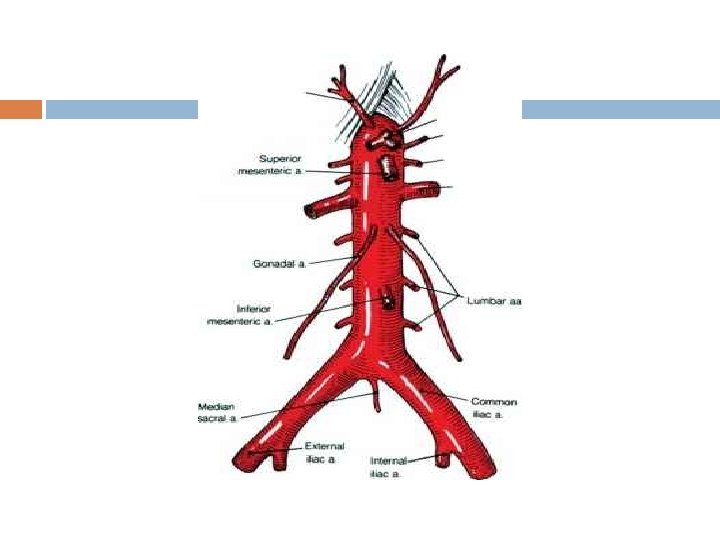

Branches of the Abdominal Aorta 1. descends slightly to the left of the vertebral column retroperitoneal Branches: Celiac Trunk (3 branches) � � � Lt gastric artery: stomach Splenic artery: spleen: stomach, & pancreas Common Hepatic Artery: liver, stomach, gallbladder, & duodenum

Branches of the Abdominal Aorta 2. Superior Mesenteric Artery: pancreas, duodenum, small intestines, most of large intestines 3. Inferior mesenteric Artery: terminal portion of the colon, sigmoid colon, & rectum

Branches of the Abdominal Aorta

5 Paired Arteries from Abdominal Aorta 1. Inferior phrenic arteries � 2. Suprarenal arteries � 3. kidneys Gonadal arteries � 5. Adrenal glands Renal arteries � 4. inferior surface of diaphragm Testicular or Ovarian Lumbar arteries � vertebrae, spinal cord, abdominal wall